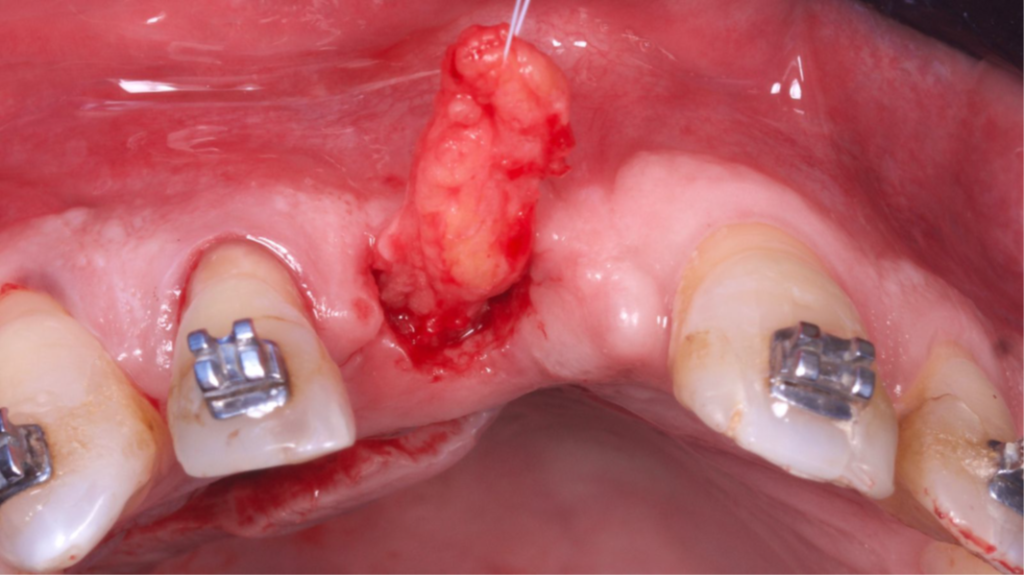

O tecido ósseo que suporta a estética rosa sofre diferentes modificações após uma extração e o biótipo gengival do paciente desempenha um papel importante na resolução multidisciplinar da instalação de um implante na zona estética. Uma alternativa viável de técnica para obter resultados estéticos e funcionais é a técnica VIP-CT (Vascularized Interpositional Periosteal Connective Tissue Flap).

O retalho VIP–CT, inicialmente idealizado para a proteção de enxertos em área anterior de maxila, pode também ser usado para aumento de rebordo na região anterior, apresentando benefícios em comparação com outras técnicas de enxertos de tecidos conjuntivos por obter um enxerto próximo ao leito receptor e completamente viável (por se manter com pedículo), bem como pode evitar a exposição de uma regeneração óssea guiada (ROG) ou enxertos ósseos de grande morbidade, como com a técnica de Khoury ou enxertos onlay.

Paciente do sexo masculino encaminhado pela Ortodontia para a instalação de um implante ao nível do dente 1.1 (Figura 1), com diastemas mésio-distais de 2mm, para utilização do implante como ancoragem absoluta e melhor andamento da movimentação ortodôntica.